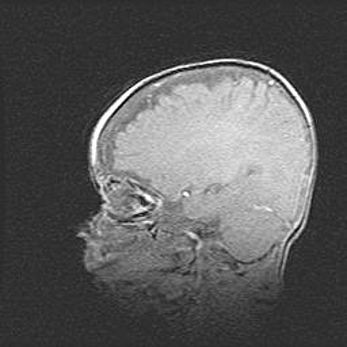

Наружная гидроцефалия с возможной атрофией височных областей.

Возраст: 28 дней

Вес: 3670 г

Пол: мужской

Окружность головы: 38 см

Срок гестации: 40 недель

Гидроцефалия головного мозга у новорожденных – это заболевание, которое характеризуется скоплением избыточного количества спинномозговой жидкости в желудочковой системе головного мозга в результате затруднения её перемещения от места выработки к месту поглощения в кровеносную систему или вследствие нарушения абсорбции. При открытой наружной форме гидроцефалии у новорожденных расширяются и переполняются субарахноидные пространства.

При нормотензивных  формах,  которые,  как  правило,  являются  следствием  перенесенных ишемических  повреждений  паренхимы  мозга,  возможно  сочетание микроцефалии  с нормотензивной гидроцефалией. В основе данных изменений лежит атрофия больших полушарий с преимущественной  локализацией  в  лобно-височных  областях.